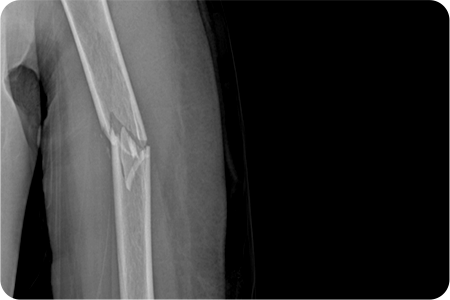

X-ray 및 CT를 통해 골절 형태와 전위 정도를 확인합니다.

골절된 뼈를 원래 위치로 맞추는 정복 작업을 진행합니다.

금속판, 나사, 고정막을 이용해 뼈를 고정합니다.

골절·외상 수술은 손상된 뼈와 조직을 정밀하게 맞추고 금속판·나사·핀 등을 이용해 안정적으로 고정하는 치료입니다.

이 과정에서 뼈의 정렬과 관절 기능을 회복하기 위한 섬세한 판단이 필요하기 때문에,

풍부한 경험을 가진 의료진일수록 정확한 교정과 빠른 회복을 기대할 수 있습니다.